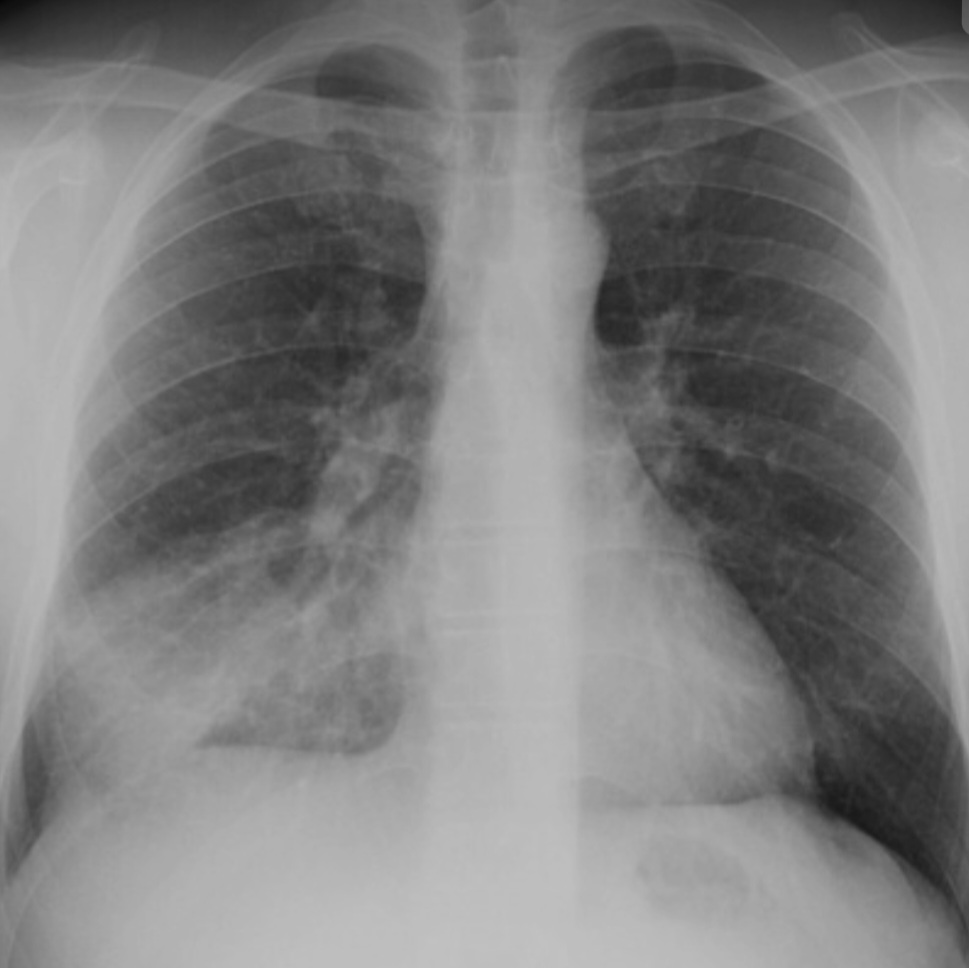

Pulmonary function tests are non-invasive tests that show how well the lungs are working. The tests measure lung volume, capacity and rates of flow. This information can help your healthcare provider diagnose and decide the treatment of certain lung disorders.

There are 2 types of disorders that cause problems with air moving in and out of the lungs:

- ObstructiveThis is when air has trouble flowing out of the lungs due to airway resistance. This causes a decreased flow of air.

- RestrictiveThis is when the lung tissue and/or chest muscles can’t expand enough.